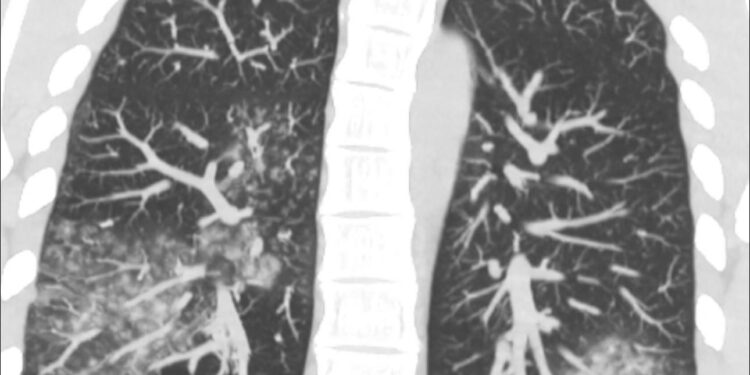

Рентгенологічні зміни неспецифічні: «матове скло», ателектази, гіперроздуті легені, іноді – консолідація. Частіше двобічні ураження», – написала вона на своїй сторінці в Фейсбук.